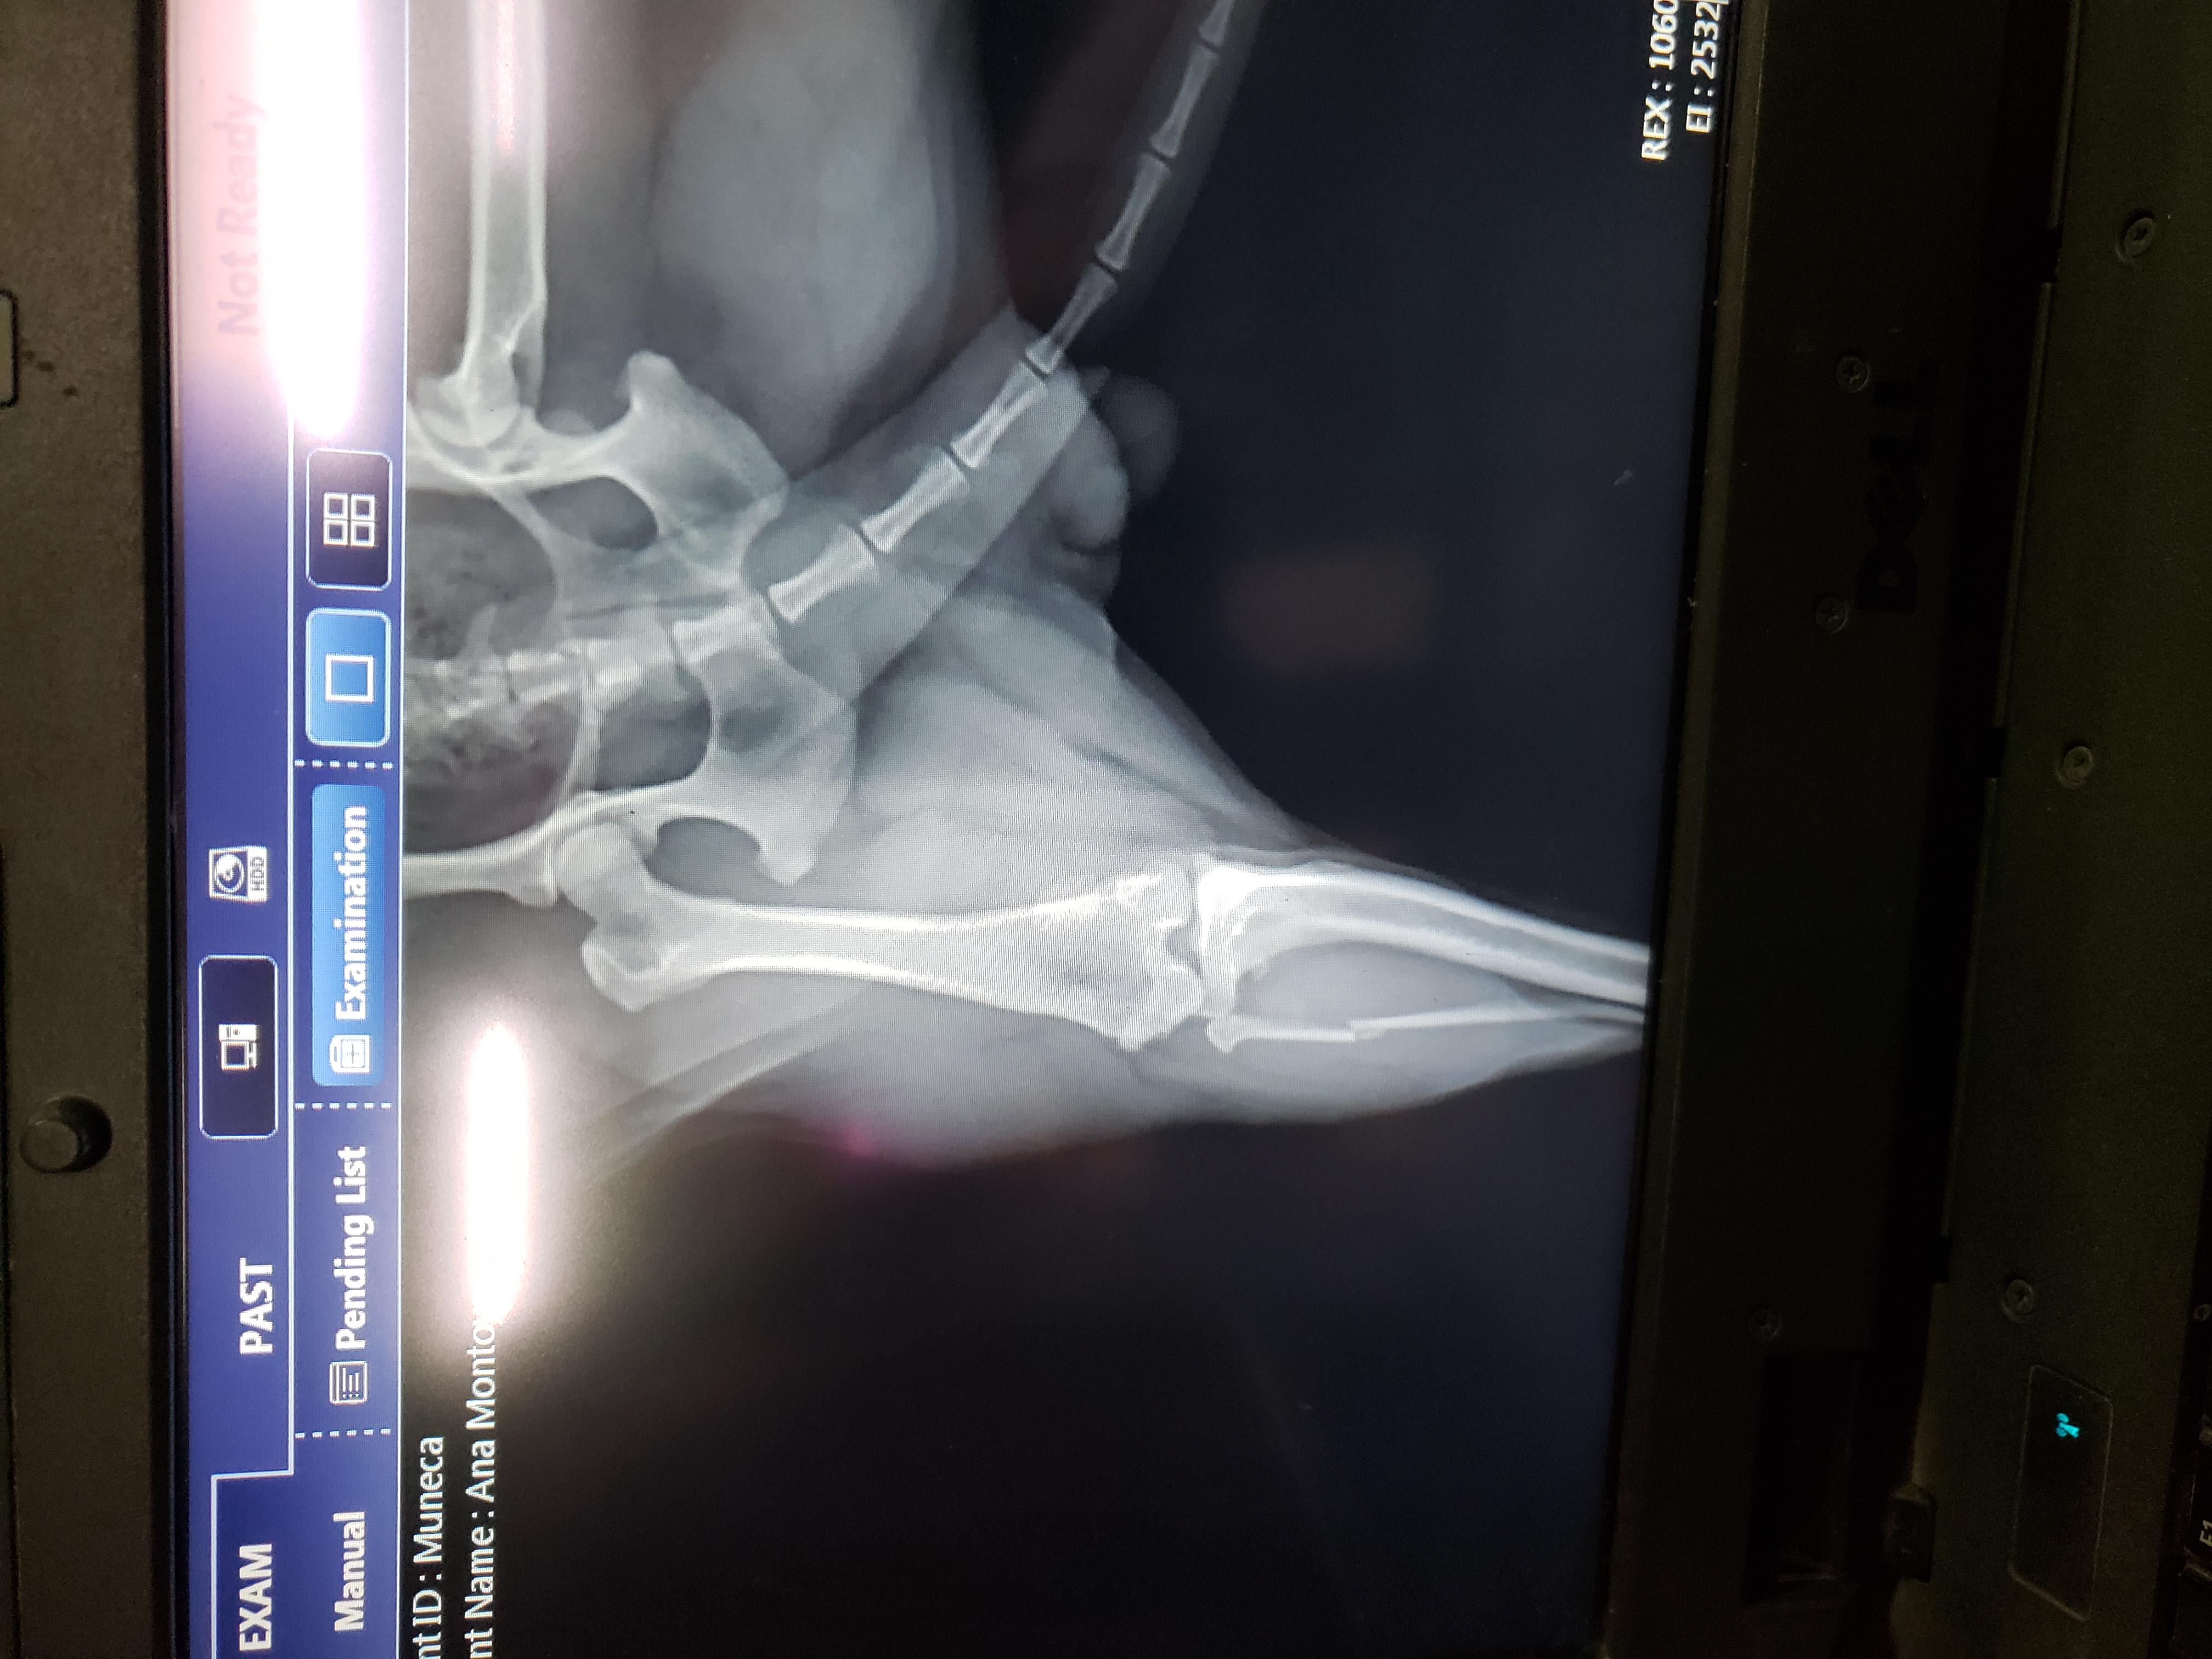

Hello my dog is limping from her hind leg. I took xrays I want an opinion

Hello and thank you for reaching out to Petco Pet Education Center, formerly Petcoach. I'm sorry to hear that Muneca is limping. Based off the radiograph, it looks like her fibula, the smaller bone in her lower leg, may be fractured. It is difficult to know for sure without an orthogonal view, but that may be the reason for her limping. I recommend restricting her activity to cage rest and leash walks only, do not let her run or play for at least 4 weeks to allow time for the bone to heal. I recommend having her evaluated by a veterinarian who can perform bloodwork and see if it is safe to prescribe her anti-inflammatory pain medications to help her feel more comfortable. NEVER give human pain medications to dogs as they can be markedly toxic. I hope this is helpful!

From the x rays it looks like the fibula is fractured. Pain relief medications (and anti-inflammatory) and cage rest is strictly needed. Usually conservative treatment has a good success rate in these cases and surgery is not an option. Please discuss with your vet the possible options in terms of medications. Hope this answer was helpful, but please do not hesitate to contact us again on the forum or by requesting a consultation if you have any more questions or to discuss it any further.